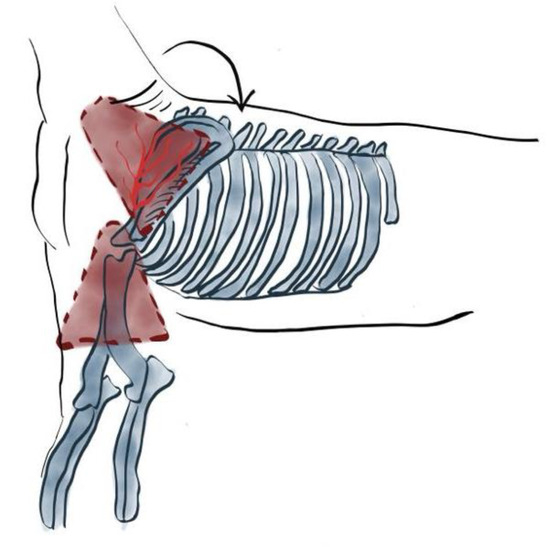

Chest Wall Resection and Reconstruction Following Cancer

by Francesco Petrella, Andrea Cara, Enrico Mario Cassina, Lidia Libretti, Emanuele Pirondini, Federico Raveglia, Maria Chiara Sibilia and Antonio Tuoro

Curr. Oncol. 2025, 32(12), 708; https://doi.org/10.3390/curroncol32120708 - 16 Dec 2025

The chest wall represents a complex musculoskeletal structure that provides protection to intrathoracic organs, mechanical support for respiration, and mobility for the upper limbs. Neoplastic diseases of the chest wall encompass a heterogeneous group of benign and malignant lesions, which may be classified [...] Read more.

The chest wall represents a complex musculoskeletal structure that provides protection to intrathoracic organs, mechanical support for respiration, and mobility for the upper limbs. Neoplastic diseases of the chest wall encompass a heterogeneous group of benign and malignant lesions, which may be classified as primary—originating from bone, cartilage, muscle, or soft tissue—or secondary, resulting from direct invasion or metastatic spread, most commonly from breast or lung carcinomas. Approximately half of all chest wall tumors are malignant, and their management remains a significant diagnostic and therapeutic challenge. Surgical resection continues to represent the mainstay of curative treatment, with complete en bloc excision and adequate oncologic margins being critical to minimize local recurrence. Advances in reconstructive techniques, including the use of prosthetic materials, biological meshes, and myocutaneous flaps, have markedly improved postoperative stability, respiratory function, and aesthetic outcomes. Optimal management requires a multidisciplinary approach involving thoracic and plastic surgeons, oncologists, and radiotherapists to ensure individualized and comprehensive care. This review summarizes current evidence on the classification, diagnostic evaluation, surgical strategies, and reconstructive options for chest wall tumors, emphasizing recent innovations that have contributed to improved long-term survival and quality of life in affected patients. Full article

Show Figures

Figure 1